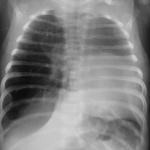

Lymphome de Hodgkin à localisation cutanée spécifique

Un homme de 25 ans consulte pour des symptômes respiratoires incluant une dyspnée, une orthopnée et une toux, accompagnés de l’apparition...